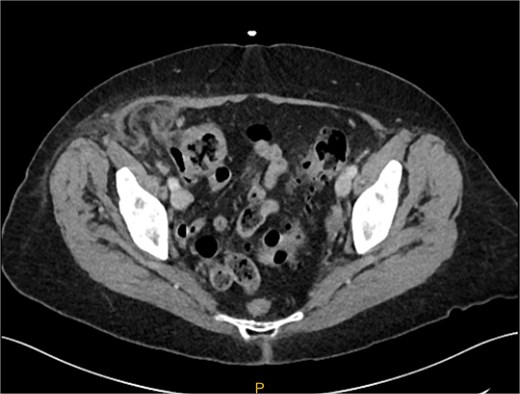

The patient was hemodynamically stable and afebrile in the emergency department. On examination, there was a palpable, non-reducible mass in her right lower abdomen that was tender to palpation. Remaining physical examination was unremarkable. Blood analysis of the patient demonstrated a normal WCC of 7.2 and an elevated CRP of 42. A CT abdomen and pelvis suggested there was a strangulated right ventral abdominal wall hernia lateral to the deep inguinal ring. The hernia contained the tip of the appendix with some free fluid and had associated fat stranding. The favoured provisional diagnosis was an incisional hernia containing her appendix due to her extensive previous abdominal surgery. Differential diagnoses included Amyand’s hernia (Fig. 1).

Preoperative CT image of right inguinal hernia. It is difficult from the images to determine if the hernia sac contains an appendix.